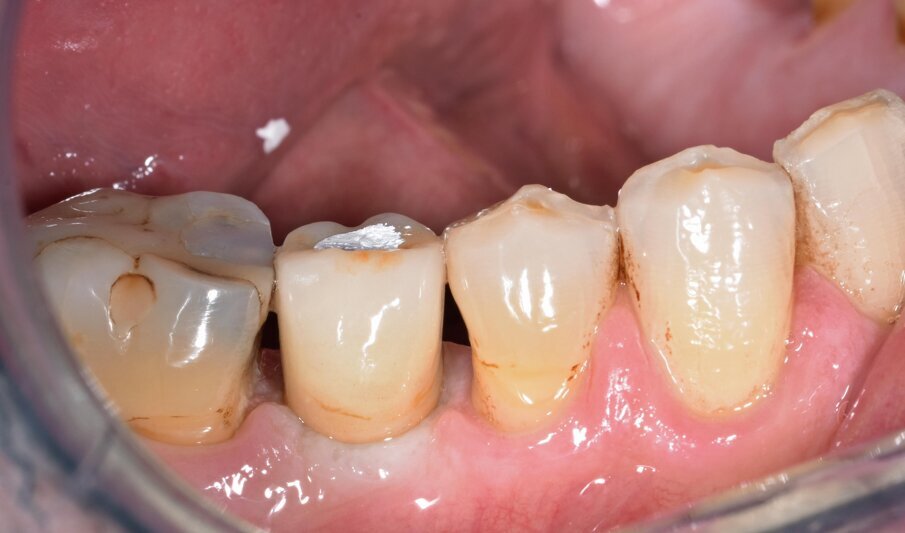

G. I. paziente di anni 50, si presenta alla nostra osservazione con una frattura longitudinale della radice dell’elemento 4.5 dovuta a infiltrazione cariosa della vecchia corona protesica. Questa situazione ha provocato nell’osso alveolare del paziente una grossa lesione che è andata ad interessare anche la corticale vestibolare. Per poter sostituire la radice con un impianto sarebbe necessario un intervento di chirurgia ossea rigenerativa ma un’alternativa meno invasiva è la rigenerazione del tessuto osseo ottenuta tramite l’estrusione forzata dell’elemento che rigenera osso durante la sua lenta migrazione grazie al legamento parodontale. In accordo con il paziente, dopo opportuna spiegazione dei benefici e dei tempi dell’approccio con estrusione ortodontica, si decide di procedere con questo iter evitando così l’intervento di rigenerativa.

In questo caso clinico la difficoltà consisteva nel fatto che si è resa necessaria l’estrazione della metà mesiale della radice fratturata e quindi nel far compiere al frammento radicolare rimasto un movimento diagonale per mezzo del quale la porzione distale rimasta con il legamento parodontale avrebbe permesso una corretta rigenerazione tissutale ossea come indicato in rosso nell’immagine radiografica.